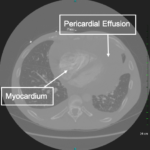

Cardiac tamponade is a rare and life-threatening condition that can be caused by trauma and various medical conditions. Failure to recognize and repair it quickly could lead to significant morbidity or even death. This case demonstrates the electrocardiogram (ECG) findings of low voltage QRS and electrical alternans in cardiac tamponade. It also highlights the classic ultrasound (US) findings of pericardial effusion and right ventricular collapse during diastole in cardiac tamponade. Classic physical exam findings of cardiac tamponade include Beck’s Triad (jugular venous distention, hypotension, and muffled heart sounds) and pulsus paradoxus. This patient only had jugular venous distention and pulsus paradoxus. The case is centered on a 52-year-old male who presented with shortness of breath, wheezing, and a productive cough with streaks of blood. A CT chest was performed which revealed a large pericardial effusion, right upper lobe lung mass, and bilateral pulmonary emboli. A bedside transthoracic echocardiogram was then performed which confirmed the large effusion as well as right ventricular collapse during diastole. Cardiothoracic surgery and interventional cardiology were consulted and both agreed to take the patient to the cardiac catheterization lab for percutaneous drainage of the effusion. Pericardiocentesis was performed and 1.7 liters of serosanguinous fluid was removed and a drain was left in place. He recovered well from the procedure and had an uneventful admission. After reviewing this case, learners should be able to recognize the diagnostic features and various causes of pericardial effusion and cardiac tamponade.